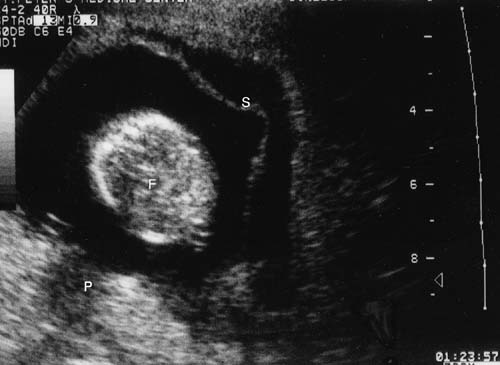

Because of the advances in ultrasound resolution, imaging, and interpretation, we recently set out to prospectively determine the diagnostic accuracy of targeted sonography in detecting abruptio placentae in patients with vaginal bleeding. The ultrasound examination targeted for the following seven sonographic features of abruption: (1) preplacental collection under the chorionic plate (between placenta and amniotic fluid) (Fig. 5); (2) jello-like movement of the chorionic plate with fetal activity; (3) retroplacental collection (between placenta and myometrium) (Fig. 6); (4) marginal collection (at the placental margin) (Fig. 7); (5) subchorionic membranous collection (between the membranes and uterine wall) (Fig. 8); (6) increased placental thickness or echogenicities (defined as greater than 4–5 cm perpendicular to the plane of the placenta throughout pregnancy (Figs. 9 and 10); and (7) intra-amniotic hematoma (collection within the amniotic fluid) (Fig. 11).

Fig. 8. Extensive subchorionic membranous collection between the placental membranes and the uterine wall on ultrasound. S, subchorionic collection; F, fetus; P, placenta.